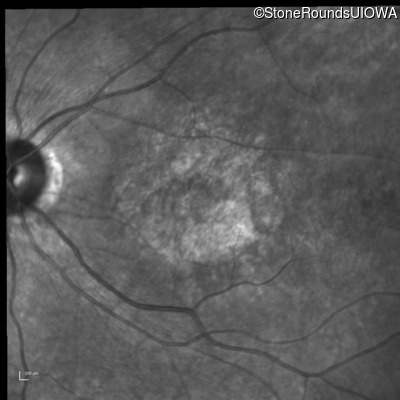

Infrared Fundus Photograph - Right - 20/200 -3

Exemplar

Infrared Fundus Photograph - Left - 20/200 -2